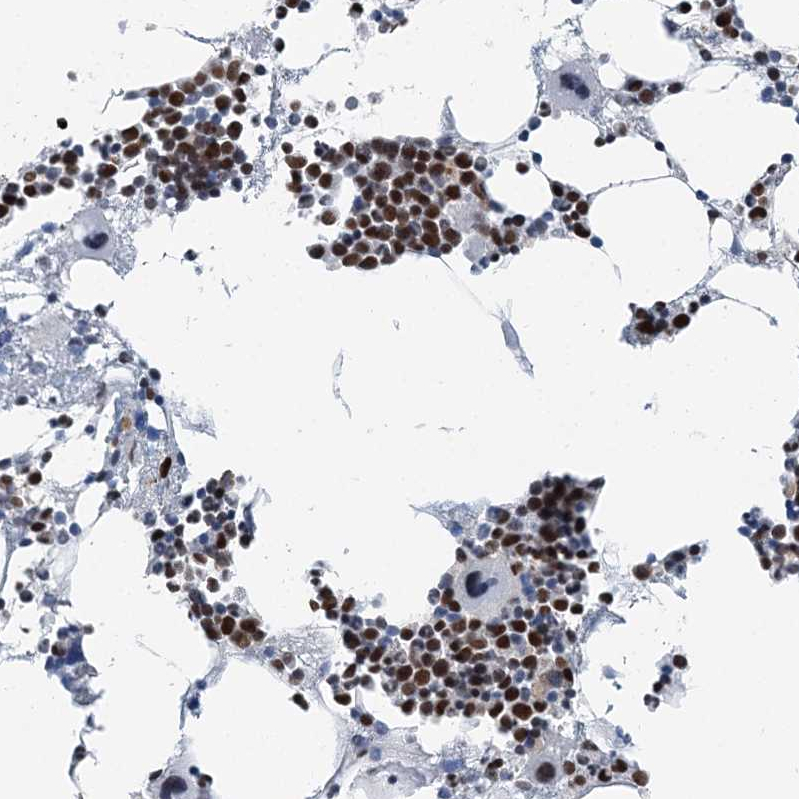

Immunohistochemical staining of human bone marrow shows strong nuclear positivity in hematopoietic cells.